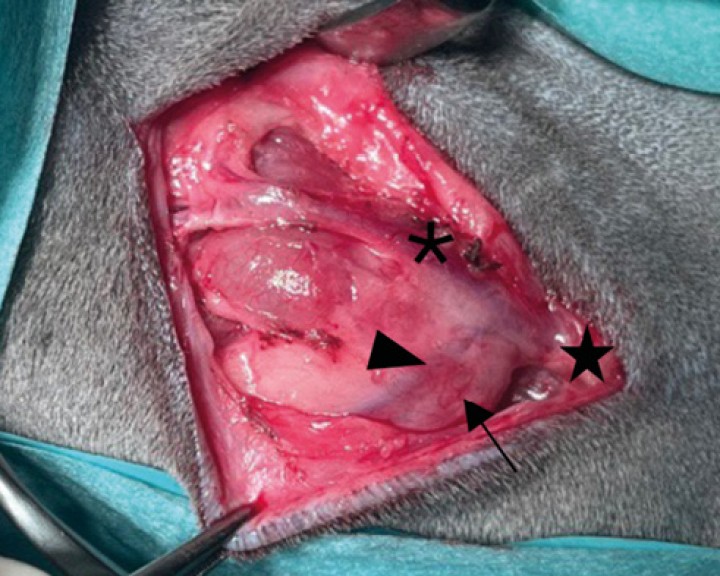

Disección de la glándula mandibular ( * ) junto con la glándula sublingual del resto de tejidos. Durante la disección es necesario realizar hemostasia mediante ligadura o diatermia de la vascularización que irriga a dicho complejo salivar. La disección del complejo debe realizarse paralela y rostralmente exponiendo los pequeños grupos de tejido salivar de la glándula sublingual hasta su aspecto más rostral. Los conductos salivales deben ser diseccionados hasta la rama lingual ( &lt; ) del nervio trigémino. Llegados a esta localización se realiza la ligadura distal del conducto mientras se tracciona ligeramente del complejo salivar con el fin de facilitar su exposición.

Disección de la glándula mandibular ( * ) junto con la glándula sublingual del resto de tejidos. Durante la disección es necesario realizar hemostasia mediante ligadura o diatermia de la vascularización que irriga a dicho complejo salivar. La disección del complejo debe realizarse paralela y rostralmente exponiendo los pequeños grupos de tejido salivar de la glándula sublingual hasta su aspecto más rostral. Los conductos salivales deben ser diseccionados hasta la rama lingual ( < ) del nervio trigémino. Llegados a esta localización se realiza la ligadura distal del conducto mientras se tracciona ligeramente del complejo salivar con el fin de facilitar su exposición.